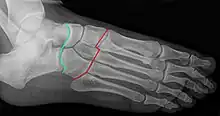

Radiographie du pied: articulation de Chopart (talo-navicualire et calcanéo-cuboïdienne) en vert et articulations de Lisfranc (tarso-métatarsiennes) en rouge.